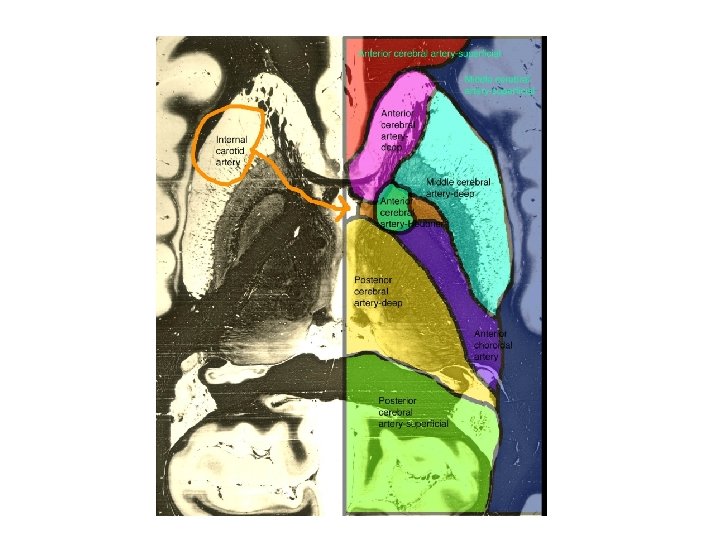

ACA MCA PCA BA VA ICA